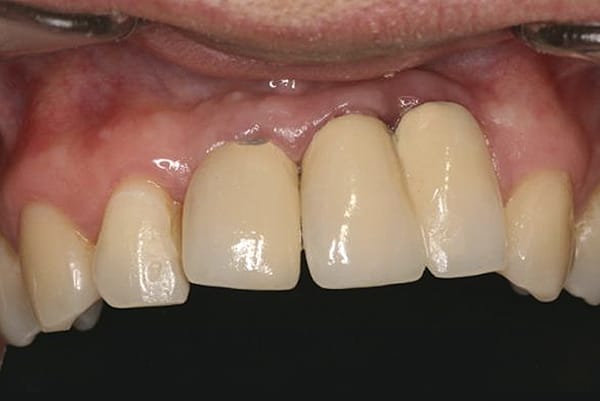

Although prosthodontists are capable of saving many complicated implant cases, the clinical results may still remain esthetically compromised. As opposed to heroic attempts to restore a misaligned implant, there are times when implant removal is a better solution. In the challenging case depicted in Figure 1 through Figure 4, it was determined that the implant, as positioned, could not be adequately restored. Two options were considered: implant removal and replacement with a properly positioned implant and implant replacement or submergence followed by the fabrication of a 3-unit fixed partial denture. The fixed partial denture would take advantage of utilizing tooth No. 8 as an abutment after removing the existing crown but would necessitate involving the virgin tooth No. 10. The surgical/prosthetic team in consultation with the patient elected to remove the implant and place a second implant. The implant was removed and a new implant was placed in the correct vertical and horizontal position using CT-guided surgery.